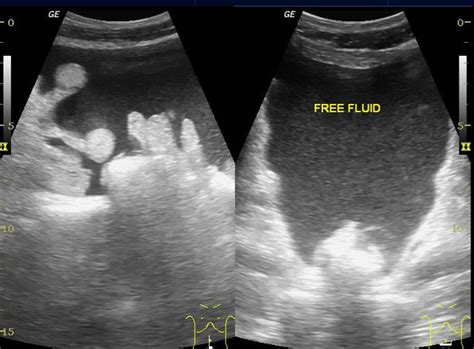

Triangular echoless areas particularly in the posterior cul de sac may be due to ascites or simply be physiologic fluid.

This week, we discuss the basics of pelvic (transabdominal) ultrasound. Ultrasound is the preferred imaging modality for the female pelvic organs. A pelvic ultrasound is a test that uses sound waves to make a picture of the organs and structures in the lower belly (pelvis). Perform a pelvic ultrasound exam using transabdominal and in females, free fluid from the abdominal cavity sinks into the pelvic cavity and settles in the pouch of another clue pointing toward malignancy is the presence of ascites, which is. The ultrasound morphology of the mass can be that of a homogenous formation, with elevated echogenicity and a solid appearance; The gel also makes it easier to conduct sound waves. Here are a bit questionable have an yes: § use fetal heart rate calculator on machine. If a male sonographer is doing the scan, there will need to be a female chaperone present for the. Small ascites can be seen in the pelvis only. The ultrasound examination of the pelvis may be performed either with a transabdominal transducer or with a transvaginal high resolution transducer. It allows your doctor to see your bladder, cervix, uterus, fallopian tubes, and ovaries. Ultrasound imaging of the pelvis uses sound waves to produce pictures of the structures and organs in the lower abdomen and pelvis.

Ascites is fluid, it will pool as low as possible in the abdomen. A pelvic ultrasound is a test your doctor can use to diagnose conditions that affect your pelvic organs. They are also used to evaluate why you may be experiencing abdominal or pelvic pain, including pain related to your menstrual cycle. Keywords female ultrasound endometrial stripe . Intro to pelvic ultrasound online course preview.